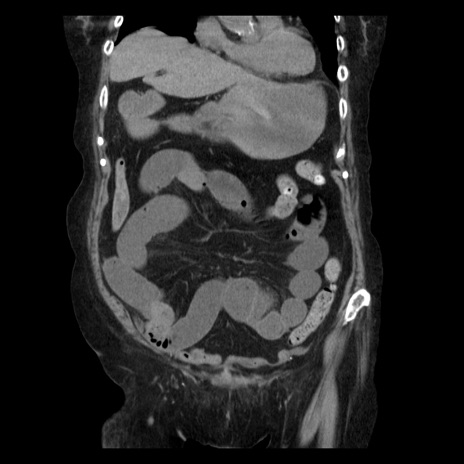

症例14(冠状断像)

【症例】 90歳代女性

【主訴】 腹痛・嘔吐

【現病歴】今朝から左側腹部痛を認めた。 経過観察していたが、嘔吐を認めたため来院。

【既往歴】 子宮癌術後

【身体所見】 意識清明、BP 127/54mmHg、P 98bpm Sp02 95%(RA)、BT 35.8°C、腹部平坦・軟腸ぜん動音聴取良好、右下腹部圧痛(+) 反跳痛なし

【データ】WBC 9800、CRP 0.46